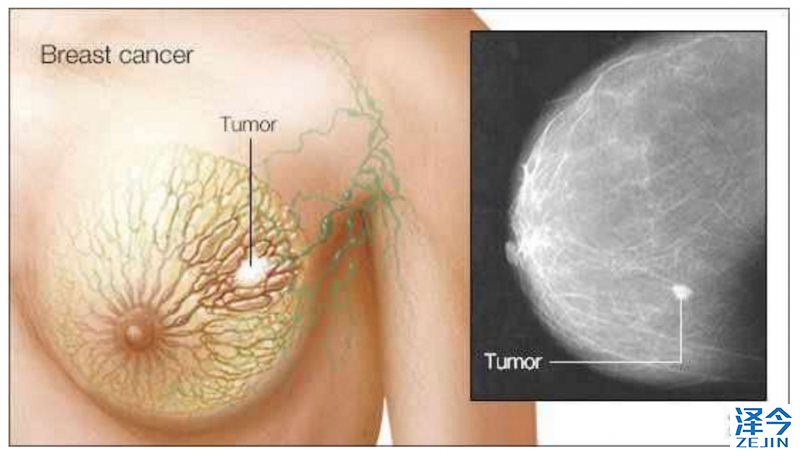

4、血癌药物对致命性三阴乳腺癌有效??

Mayo Clinic最近一项研究发现,FDA批准用于治疗骨髓增生异常综合征的药物可能有助于治疗三阴乳腺癌,这是最具侵袭性和致命性的乳腺癌之一。

研究人员发现FDA批准用于治疗某些血液癌症的药物5-氮杂-2'-脱氧胞苷(地西他滨)可以显着抑制三阴乳腺癌的生长,并且重要的是在对化疗耐药的肿瘤中也可见到这种效应。Mayo研究员Liewei Wang博士说:“非常需要为三阴乳腺癌确定更多的治疗方案,这是最难治疗的乳腺癌亚型之一。这项研究证明我们可以利用现有的许多FDA批准的药物,了解其机制来扩大其他癌症的使用范围。”

研究从用化疗治疗的乳腺癌患者产生患者衍生的异种移植物(永生化乳房肿瘤细胞)。在来自BEAUTY的活体异种移植物中发现,当存在DNA甲基转移酶蛋白质时,地西他滨在低负荷治疗剂量下对三阴性乳腺癌有效。低剂量会导致较低的毒性,并可能使药物使用更长时间,所有这些都可能有助于实现更好的治疗效果。

Goetz博士表示,正在计划研究地西他滨在一项名为BEAUTY2的前瞻性临床试验中的影响,该试验侧重于对化疗耐药的三阴性乳腺癌患者。